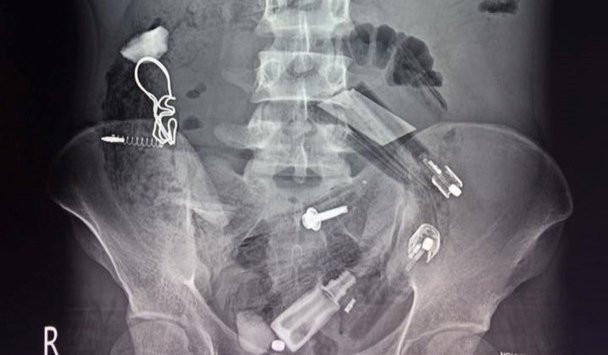

Các bác sĩ chụp Xquang và phát hiện rất nhiều dị vật trong cơ thể bệnh nhân

Kết quả chụp X quang cho thấy, trong dạ dày bệnh nhân có rất nhiều dị vật nên chỉ định phẫu thuật. Trong quá trình thực hiện, các bác sĩ đã lấy ra rất nhiều dị vật như bật lửa, lò xo bút bi, bút bi, thìa nhựa, lá cây, vỏ kẹo, vỏ thuốc, đinh…, tổng cộng hơn 30 dị vật.